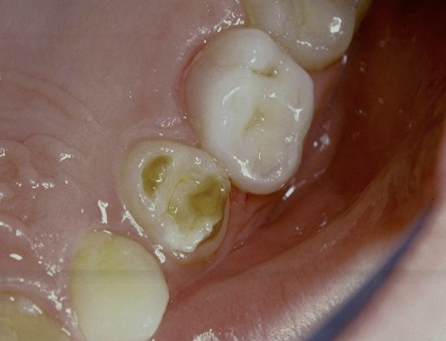

AD, AR, X-linked; both deciduous and permanent dentition are diffusely involved, affects enamel (soft, thin, easily damaged, susceptible to decay), dentin is exposed

amelogenesis imperfecta (AI)

Types of AI

hypoplastic (pitted), hypomaturation/ hypocalcification (snowcapped) AI with taurodontism

what type of AI

hypomaturation (snowcapped)

what type of AI?

hypoplastic (pitted)

Clinical appearance of AI

yellow-brown to white pitted lesions, open bite, loss of contact